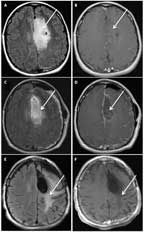

FIGURE 4

MRI of a 35-Year-Old Woman With a Grade II Oligodendroglioma, IDH1-Mutant, 1p/19q Codeleted

A 35-year-old woman presented with a generalized seizure. An MRI revealed a well-circumscribed, minimally enhancing lesion within the left frontal and parietal lobes (Figures 4A and 4B). The patient underwent gross total resection (Figures 4C and 4D), and pathology revealed a grade II oligodendroglioma. She was treated adjuvantly with 6 cycles of PCV followed by involved-field radiation. She has been progression-free for > 12 years; however, her MRI demonstrated extensive fluid-attenuated inversion recovery (FLAIR) changes consistent with treatment effect (Figures 4E and 4F). During treatment, she developed significant cognitive impairment, with poor attention and short-term memory loss, and these issues have not resolved. She could no longer work as an accountant, and she has remained on long-term disability since her diagnosis. Retrospectively, her tumor was found to be IDH1-mutant, 1p/19q-codeleted.